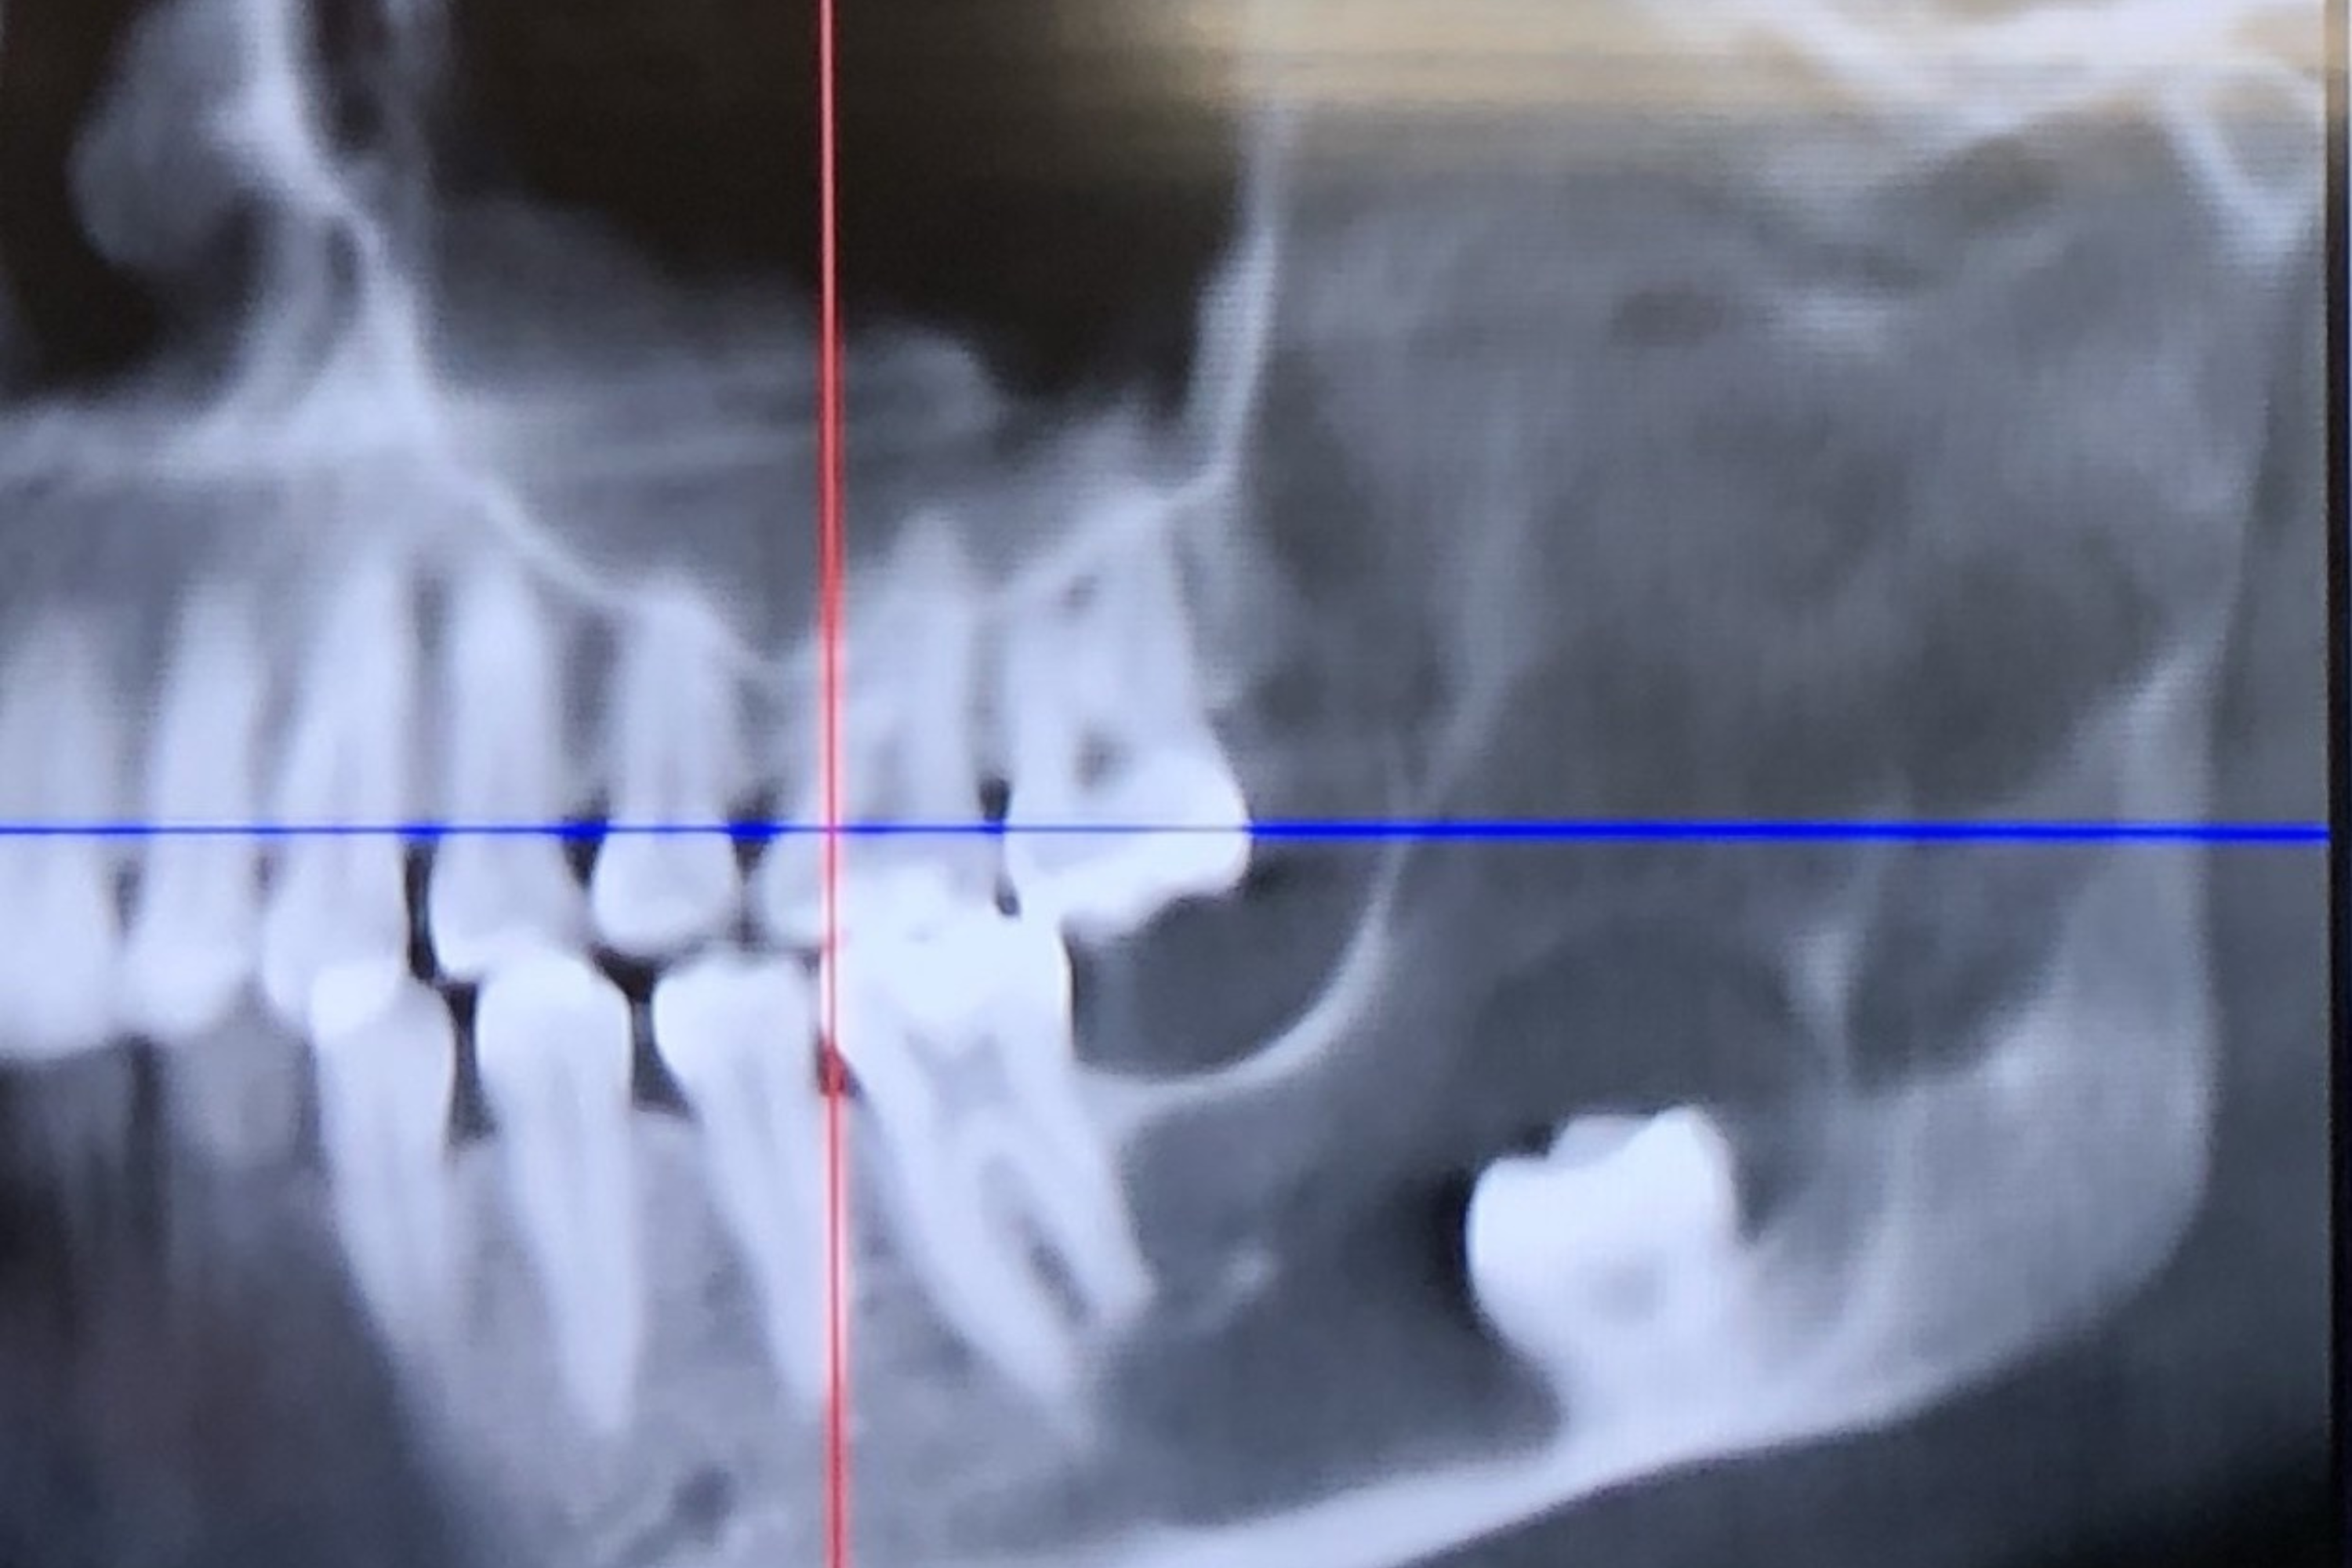

A Florida mother named Andrea discovered she had a rare and serious jaw cyst during a dental appointment she thought was for a wisdom tooth. The cyst had significantly weakened her jawbone, leading to an intensive medical treatment process. Over 16 months, Andrea went through procedures to manage and eventually remove the cyst, allowing her jaw to heal.

• Dentists found a rare cyst in her jaw from a scan, which had damaged her jawbone.

• The cyst was called an odontogenic keratocyst, known for its aggressive growth.